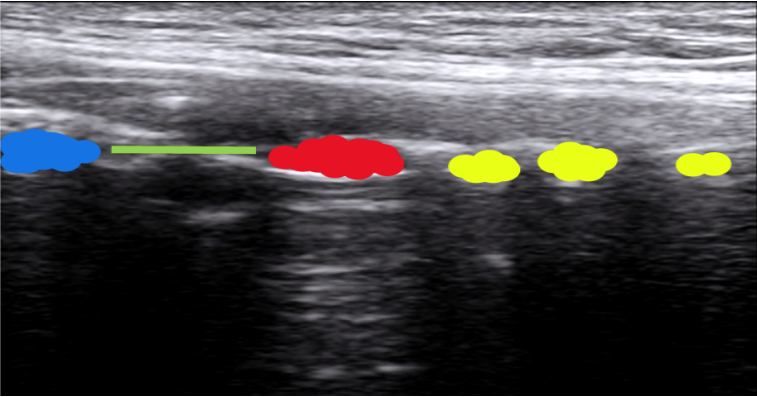

7. 食管平面的扫查

我们嘱患者头转向右侧,在胸骨上切记偏左的位置,以高频线阵探头做横向扫查,可以发现颈段食管的超声影像。图11中黄色区域为气管软骨环,蓝色区域为食管,红色区域为颈内动脉。

图片

图11  食管平面的扫查